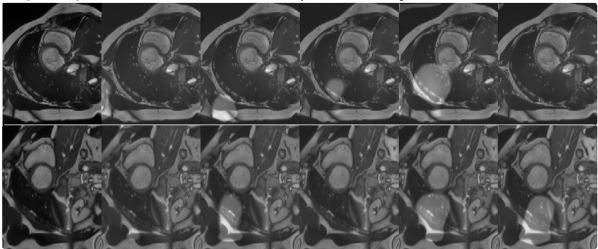

(a) image ()

(b) additive intensity

(c) transformed

field ()

image ()

(i) Transformed images are obtained by applying additive intensity fields produced by Generator .

(ii) Transformed images are obtained by applying random contrast and brightness values.